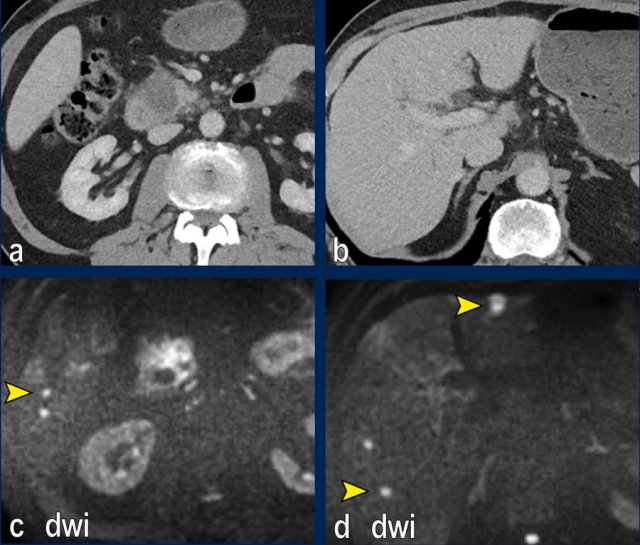

Images

The images show an axial CT (a,b) with a resectable tumor in the pancreatic head, with no signs of liver metastases.

The patient was randomized for neaoadjuvant chemoradiotherapy in the PREOPANC-2 trial.

MRI for radiotherapyplanning (DWI shown in c,d) within several weeks of CT showed over 10 liver metastases.